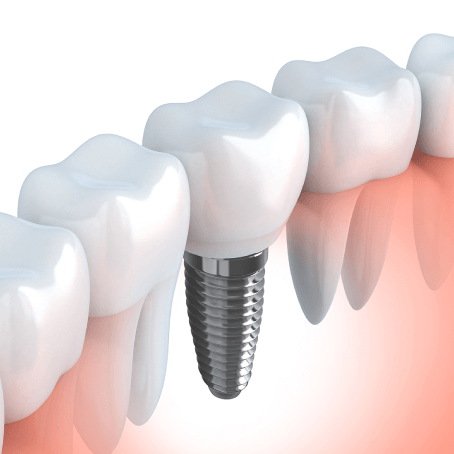

インプラントとは、人工歯根療法とも言われ、歯が抜けたところに歯の根っこにあたる部分を埋入し、その上に人工の歯(ブリッジやクラウン)をかぶせる治療方法です。入れ歯(義歯)よりも、自分の歯と同じような感覚で噛めるようになります。小林歯科医院では、インプラント治療が初めてという方も、患者様の疑問や不安を解決した上で治療に進みますので安心して治療を受けていただくことが可能です。

インプラントのメリット・留意点

メリット

• 顎の骨に直接人工歯根を埋め込むので、ご自身の歯と同等に噛む機能が回復する

• 周りの健康な歯を削る必要がない

• ご自身の歯に近い見た目を手にいれることができる

• 取り外しの煩わしさがありません

留意点

• 保険適用外のため治療費は高額になります

• 治療期間がブリッジ、入れ歯に比べて長くなります

• 全身疾患等の問題があると治療できない場合があります

• 手術が必要になります